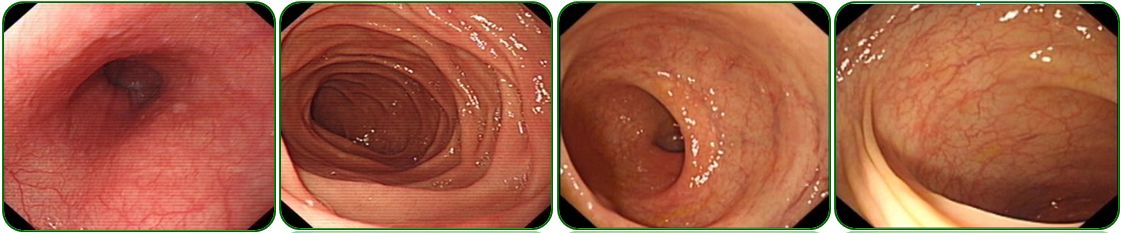

胃镜、肠镜未见异常,如图6;

肺部CT提示双肺纹理增多、左侧胸腔少量积液,如图7a-b;

腹部彩超示腹腔积液,如图7c。

图6 胃镜、肠镜检查

图7 胸部CT及腹部彩超检查

回归本例患者在门诊给予促进胃肠动力及补充消化酶治疗效果欠佳,因此行腹部彩超检查,提示腹腔积液,门诊收住院进一步检查。由于患者上腹部胀痛,进食后明显,查体剑突下轻压痛,毫无疑问胃镜检查必须做,腹腔积液患者也需要排除肠道肿瘤,因此肠镜也需要完善,所幸的是胃肠镜检查均未发现异常。

常规胸片检查提示胸腔积液,因此进一步行肺部CT检查,提示肺部CT提示双肺纹理增多、左侧胸腔少量积液,似乎本例和例2非常相似,同时胸腹腔积液。完善了腹部彩超、肝炎病毒学和PPD试验等检查,初步排除了肝硬化和结核菌感染,也未发现肿瘤征象。那么到底是什么原因呢?